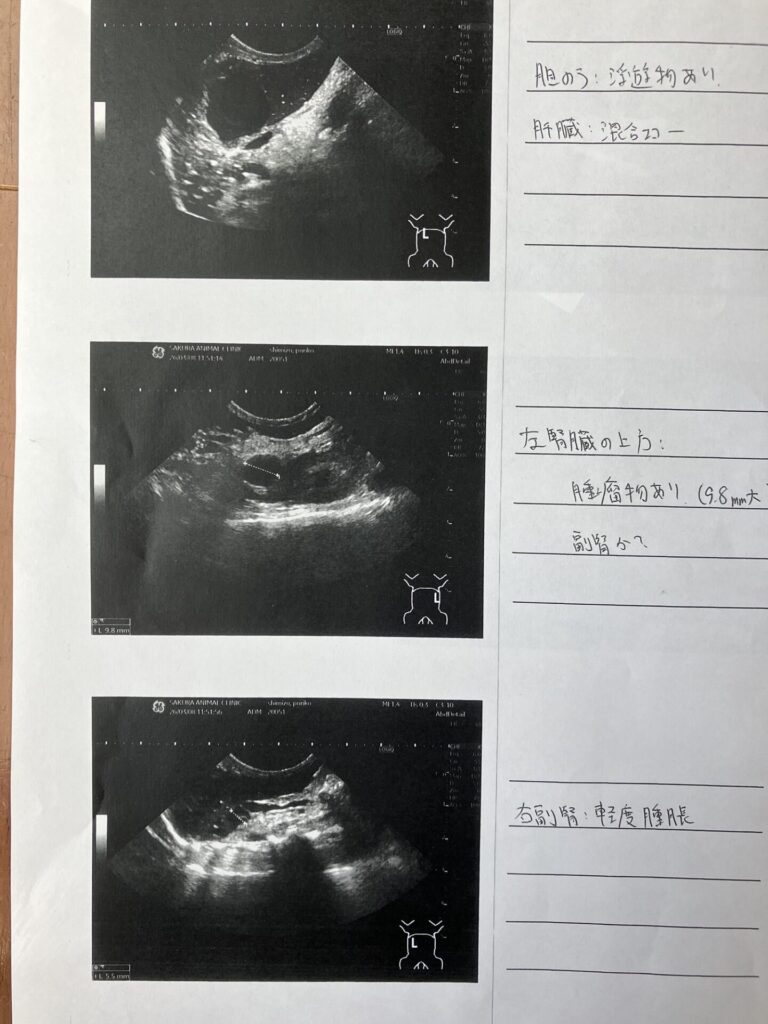

動物病院での検査結果(レントゲン)

レントゲン検査の結果、以下の診断を受けました。

・胆のうに浮遊物あり

・肝臓が混合エコー(状態が不均一)

・左腎臓上に約9.8mmの腫瘤(副腎の可能性)

・お腹にガスが溜まっている